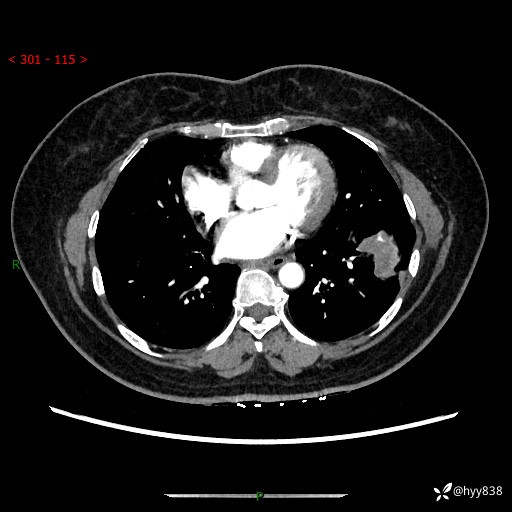

【现病史及既往史】:患者自诉2月前体检发现肺结节(左肺下叶约17mm,右肺上叶4mm),未予特殊处理,2024-10-12当地市第五医院门诊复查胸部CT提示右下肺结节(大小约3.3cm*3.9cm),患者无咳嗽、咳痰,无畏寒、发热、盗汗,无咯血,无胸闷、胸痛、呼吸困难,无恶心、呕吐,无腹痛、腹胀、腹泻等不适,现为求进一步诊治,门诊以“孤立性肺结节”收住我科。 患者本次起病来精神、食欲、睡眠尚可,大小便正常,体力、体重无明显变化。

【检查】:胸部CT增强检查